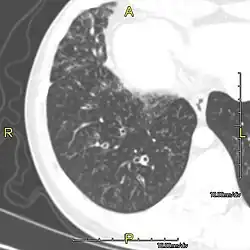

Sagittal CT image showing "tree in bud" appearance of mucous impaction in distal small airways related to primary ciliary dyskinesia

CT image showing dilated and thickened medium-sized airways (bronchiectasis) in a patient with Kartagener syndrome

Oblique sagittal CT image showing lower lobe cylindrical bronchiectasis in the same patient

Around 80% of people with primary ciliary dyskinesia experience respiratory problems beginning within a day of birth. Many have a collapsed lobe of the lung and blood oxygen low enough to require treatment with supplemental oxygen.[1] Within the first few months of life, most develop a chronic mucus-producing cough and runny nose.[1] The main consequence of impaired ciliary function is reduced or absent mucus clearance from the lungs, and susceptibility to chronic recurrent respiratory infections, including sinusitis, bronchitis, pneumonia, and otitis media. Progressive damage to the respiratory system is common, including progressive bronchiectasis beginning in early childhood, and sinus disease (sometimes becoming severe in adults). However, diagnosis is often missed early in life despite the characteristic signs and symptoms.[2] In males, immotility of sperm can lead to infertility, although conception remains possible through the use of in vitro fertilization, there also are reported cases where sperm were able to move.[8] Trials have also shown that there is a marked reduction in fertility in females with Kartagener's syndrome due to dysfunction of the oviductal cilia.[9]